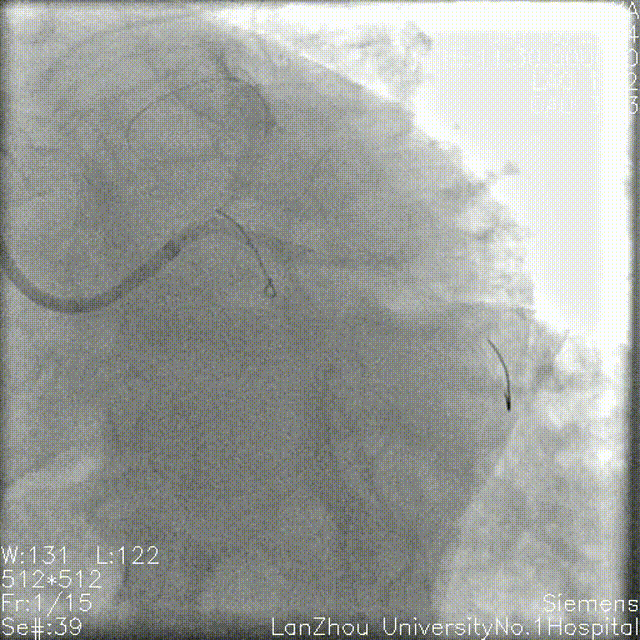

GC:7F EBU 3.5 前降支、回旋支分别植入导丝 1.5*15mm球囊 12atm分别预处理回旋支开口、近端,血流恢复TIMI III级。

2.0*20mm球囊 再次扩张,造影血管显影更清晰。

2.0*15mm双导丝球囊 14atm修饰回旋支开口-左主干末端。

2.5*12mm NC球囊高压扩张回旋支近端复查造影提示狭窄缓解。

2.5*12mm、 3.0*12mmNC 球囊高压扩张前降支,复查造影提示狭窄明显减轻。